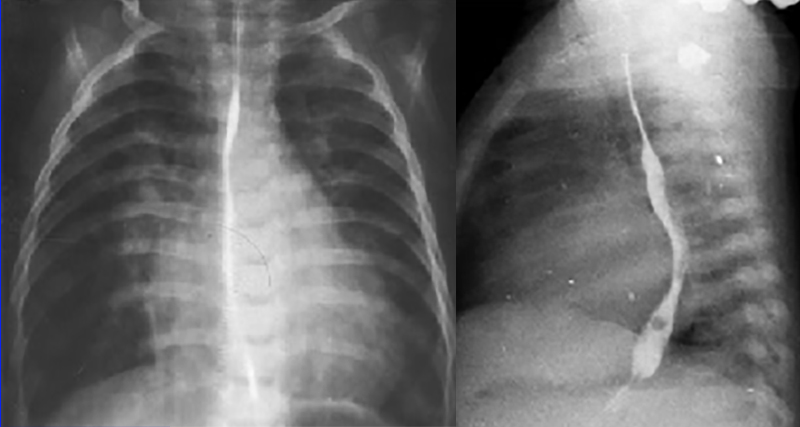

LA / Biventricular Enlargement, ↑ Pulmonary Arterial Vascularity

These chest X rays demonstrate left atrial enlargement, right and left ventricular enlargement and increased pulmonary arterial vascularity.

In the PA view, left atrial enlargement is reflected by elevation of the left main stem bronchus.

It is more definitively demonstrated in the lateral view by the posterior deviation of the barium filled esophagus.

The PA view also demonstrates right and left ventricular enlargement, based on the large cardiac shadow significantly greater than fifty percent of the thoracic diameter, extending both leftward and rightward.

Increased pulmonary arterial vascularity is reflected by the dilated central pulmonary arteries and the prominent distal arterial vascular markings.